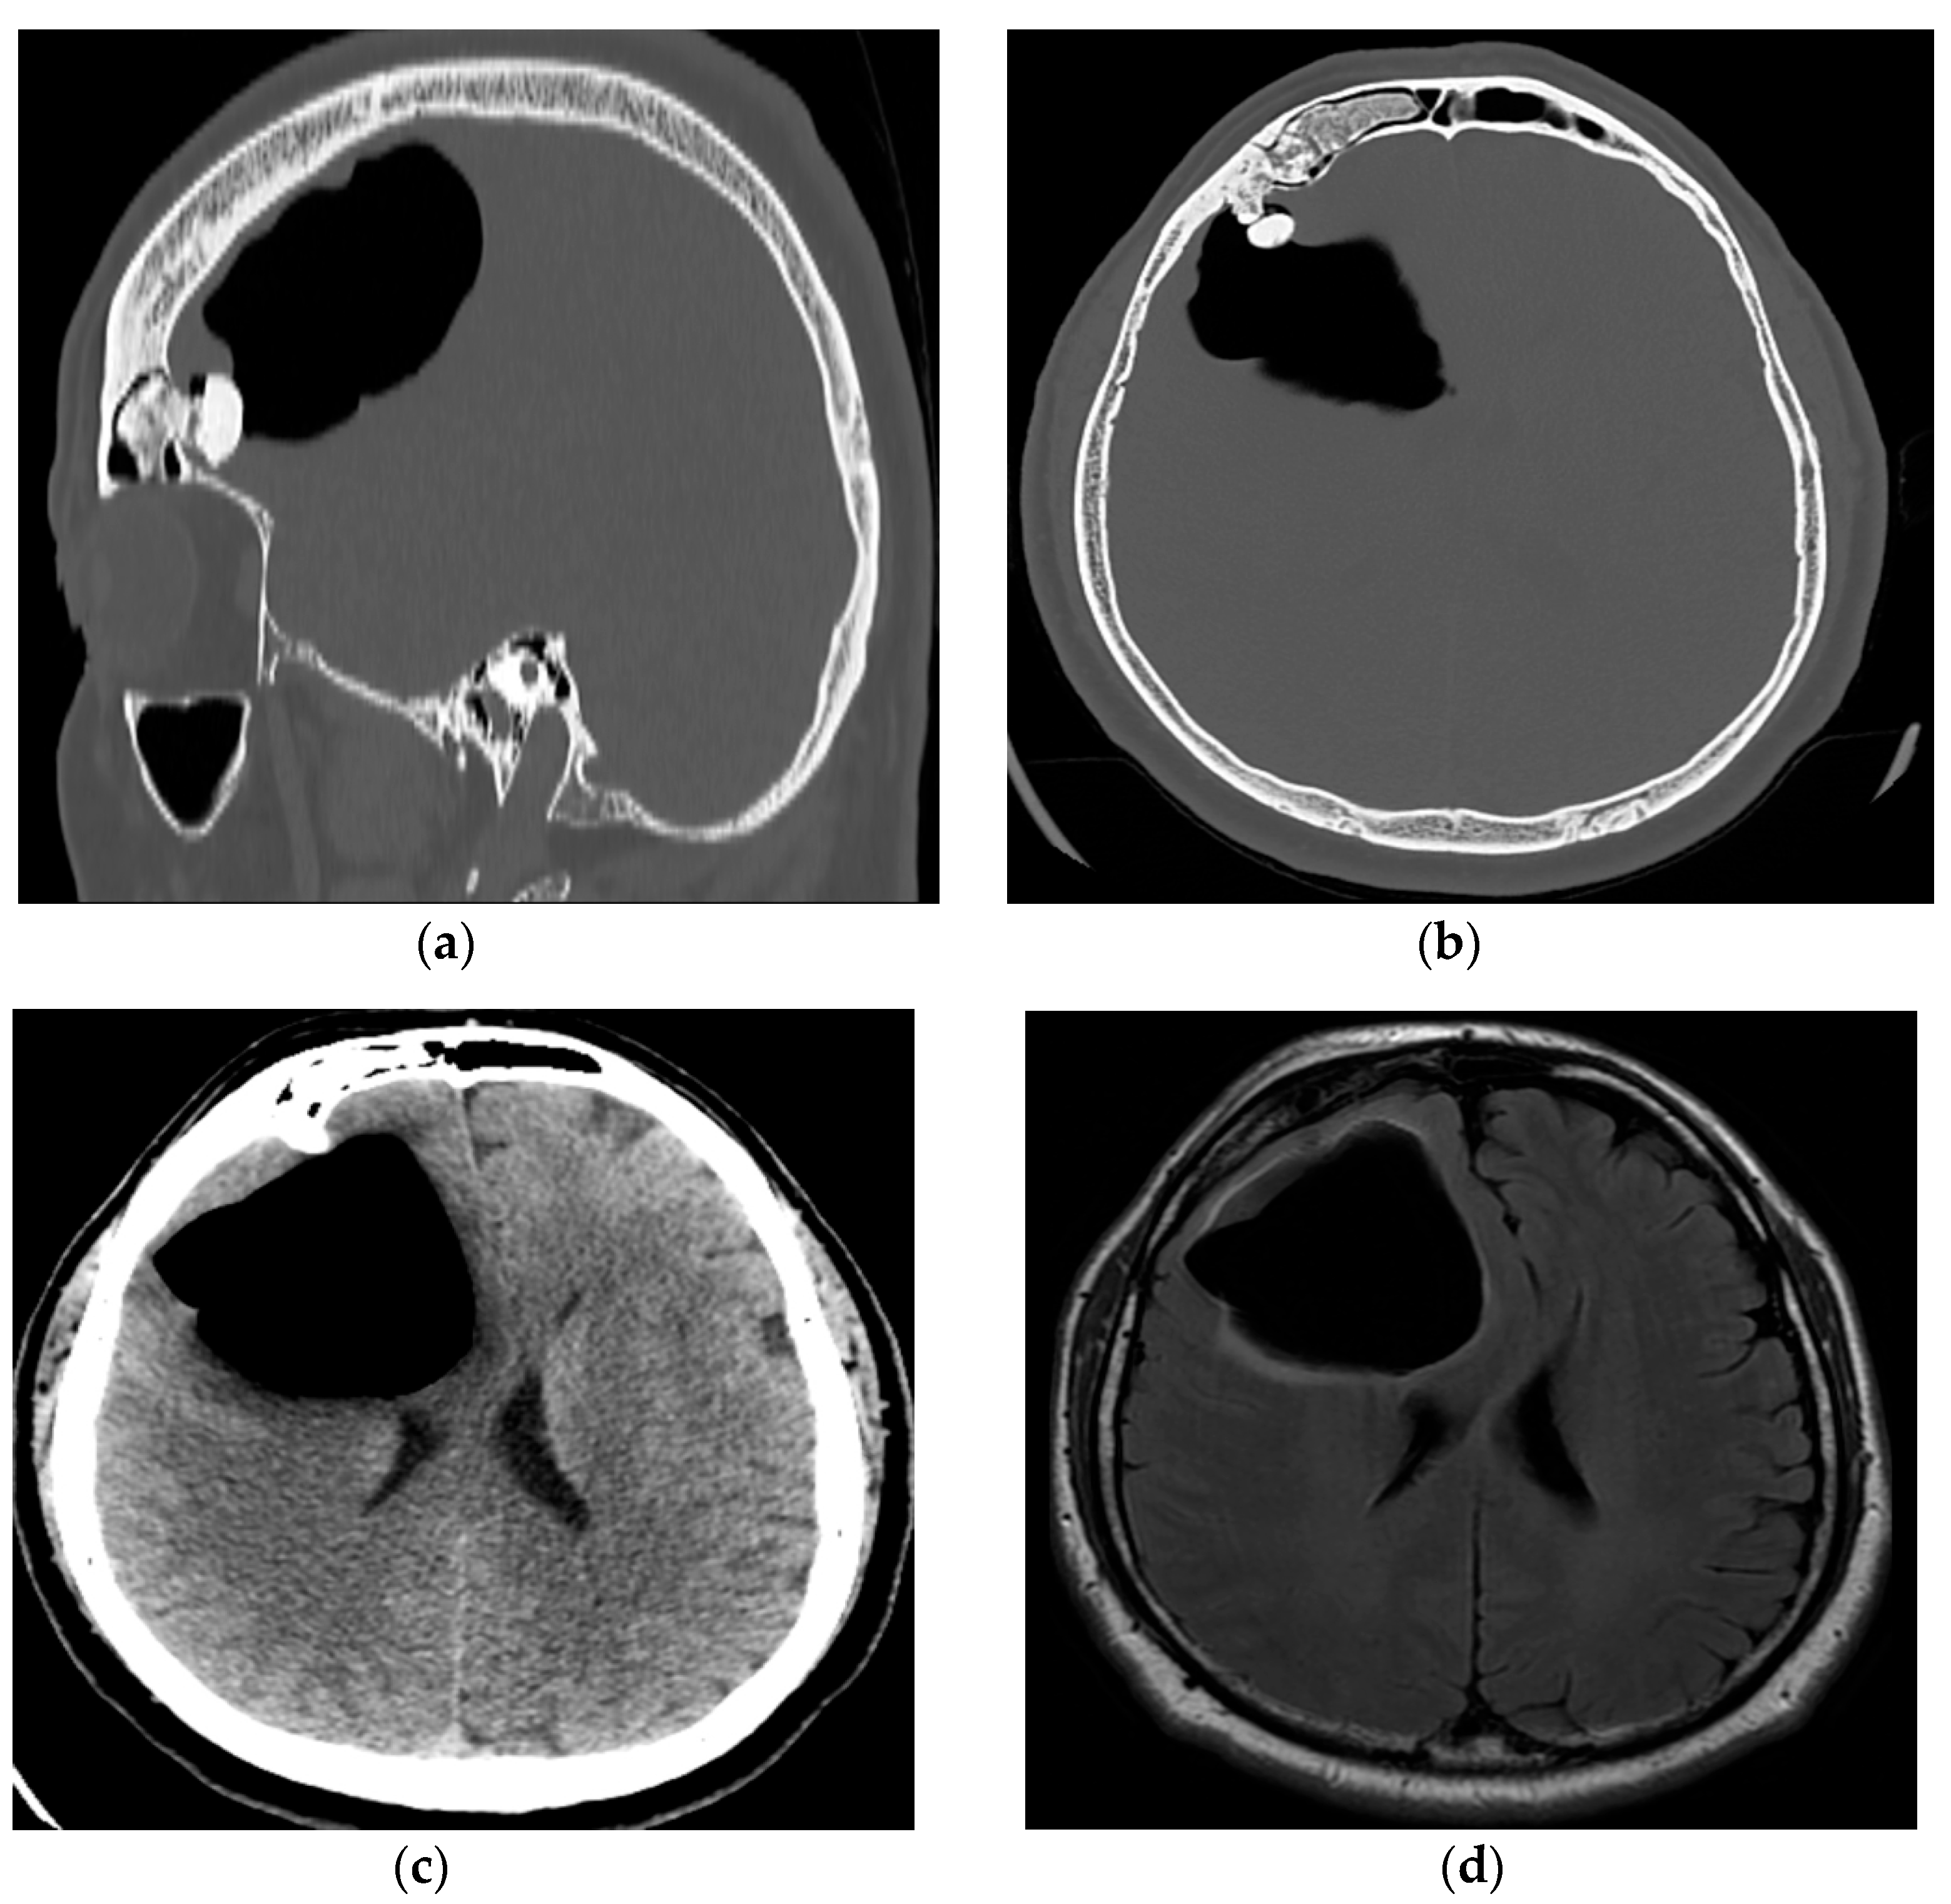

2. Case Presentation